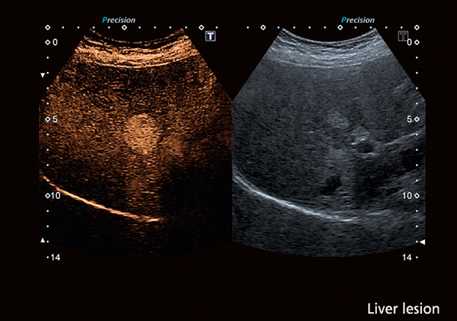

Улучшение отображения кровотока органа в режиме серой шкалы может способствовать обнаружению образований и дифференциации нормальных и патологических областей с использованием многих из тех критериев, которые уже рутинно используются в КТ и МРТ. На рисунке пример улучшенного обнаружения образования в печени, которое стало возможным благодаря импульсной инверсной гармонической визуализации (специальный режим УЗ изображения, применяемый при исследовании с контрастом).